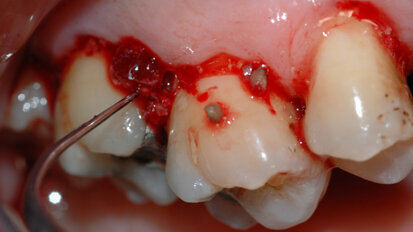

Il controllo chimico della placca nella terapia delle malattie parodontali e perimplantari placca-indotte

Le patologie infettive che colpiscono i tessuti parodontali e perimplantari hanno un comune primum movens eziopatogenetico: l’accumulo di placca ...